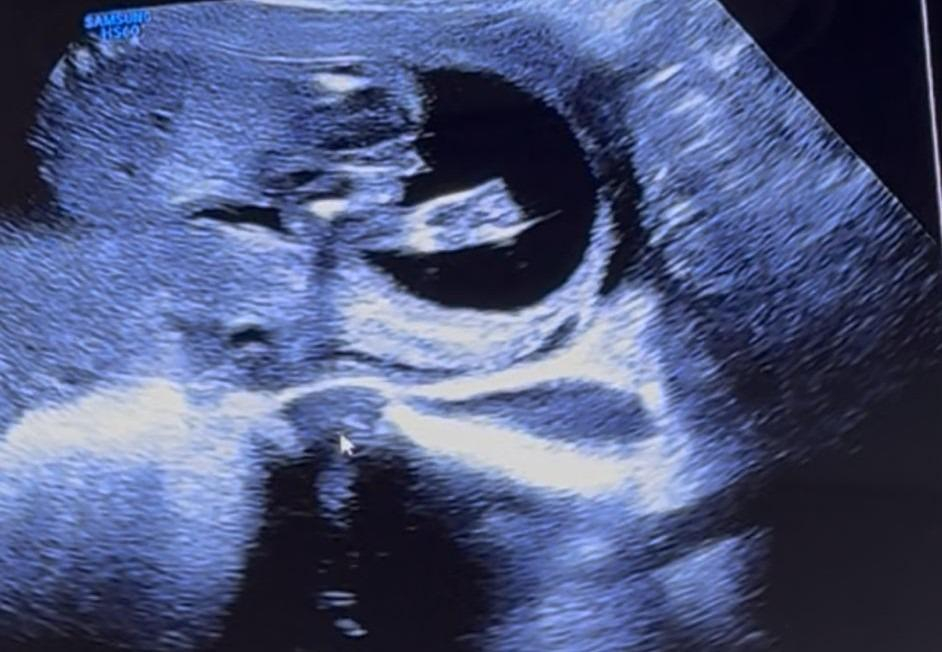

Mädchen oder Junge SSW17

Hallo meine Lieben, waren heute beim Ultraschall SSW17

Das Geschlecht spielt bei uns keine Rolle, da wir bereits einen Jungen und ein Mädchen haben.

Aber aus reiner Neugier, was meint ihr anhand der Bilder, Mädchen oder Junge